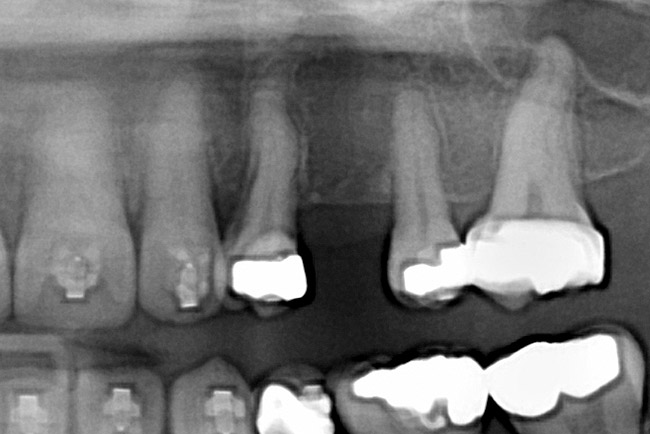

Fig 2 (and Fig 3). Corticotomy SFOT. The patient presented with unesthetic anterior bridgework that was placed at age 14 to compensate for congenitally missing Nos. 7 and 10.

Fig 3 (and Fig 2). Corticotomy SFOT. The patient presented with unesthetic anterior bridgework that was placed at age 14 to compensate for congenitally missing Nos. 7 and 10.

Fig 4. Note gingival inflammation caused by biologic width violation. Provisional restorations were placed on Nos. 6, 8, 9, and 11, and corticotomies were performed from Nos. 3 to 14.